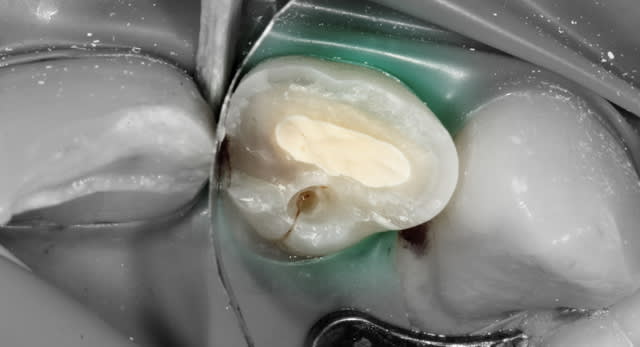

Une pulpotomie partielle est réalisée afin d'éliminer le tissu le plus contaminé. De la Biodentine est utilisée ; son avantage par rapport au MTA est de ne pas noircir. Du CaOH aurait un taux de succès moindre.

Si le patient avait été vu le jour même du trauma, une exérèse pulpaire a minima (1 mm pour loger le matériau) aurait été suffisante.

- L'éviction du tissu pulpaire est réalisée avec une fraise-boule acier sur contre-angle bague bleue. La fraise est stérile : n'a rien touché d'autre avant.

La quantité de tissu à enlever dépend de l'ancienneté de l'exposition. C'est "empirique" : on imagine la profondeur de tissu infecté depuis l'exposition. 1 mm si le trauma a quelques heures, toute la pulpe camérale si 24h, toute la pulpe si plus de 48-72h.

Plus la pulpe est jeune et la dent immature, plus on est conservateur. Et inversement.

- L'hémostase est faite avec un coton stérile (des boulettes de coton dans un sachet passé à l'autoclave).

- Pour la pose de la biodentine : le matériau est tixotrope, il se fluidifie dès qu'on le vibre. Je le place dans la cavité puis en le tapotant délicatement, il "fond" et se répartit sans qu'on ait à le fouler.

- Le volume de Biodentine est dans la chambre et n’interfère donc pas avec le collage : j'ai juste nettoyé le pourtour et fraisé l'excès sur le dessus.